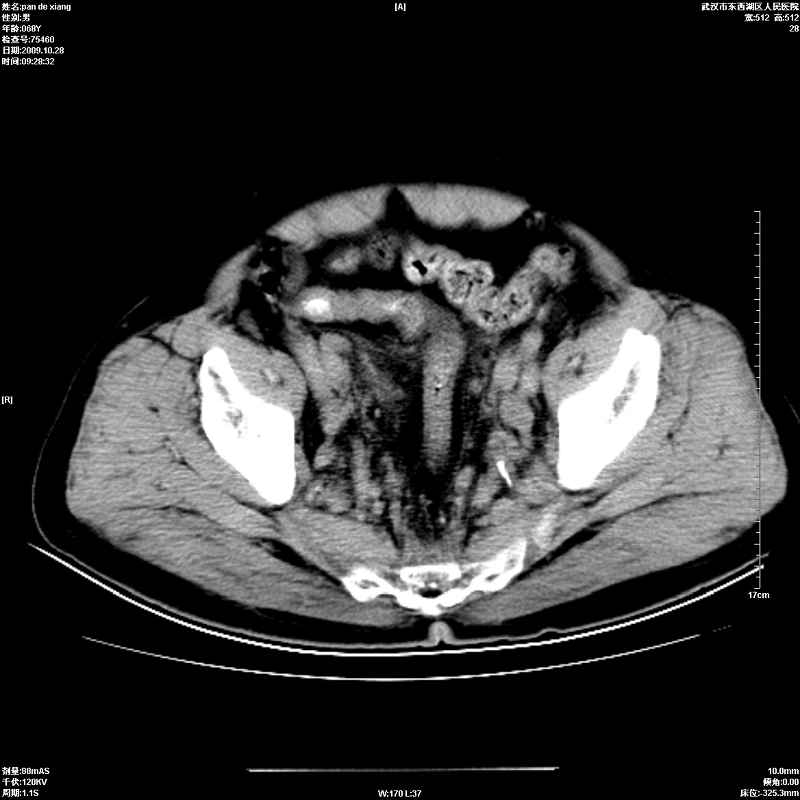

以下是引用杀毒软件在2009-10-28 20:41:00的发言:[br]结合临床考虑---白血病双肾改变或淋巴瘤。

以下是引用zxl51642在2009-10-29 9:59:00的发言:[br]结合临床“单克隆免疫球蛋白血症”,考虑双肾为继发损害并肾功能不全(尿中大量igg及少量iga、igm等大分子免疫球蛋白滤出所致继发损害),椎前软组织肿块为髓外造血。与浆细胞瘤有区别,平扫时有战友说的很清楚。